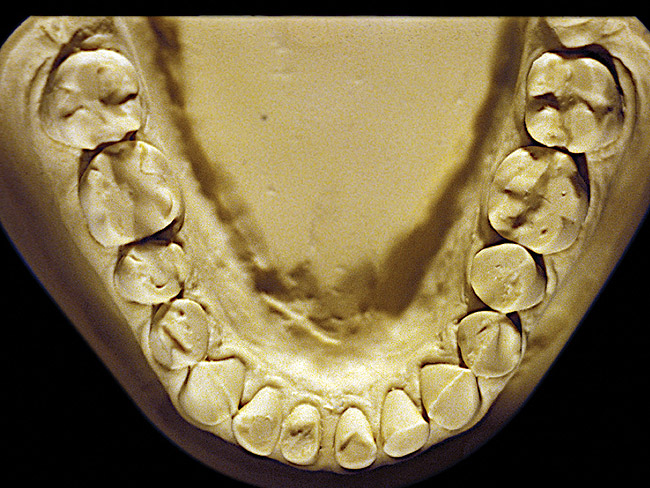

Figure 6  Moderate NCLTS from bruxism, mandibular arch.

Figure 6

The patient shown in Figure 3 and Figure 4 exhibited severe NCLTS from bruxism. Examination of the casts indicated that the NCLTS was progressively greater toward the anterior teeth. Cupping and cratering was not present because there was no secondary cause. Figure 5 and Figure 6 detail another bruxism patient, but to a lesser degree and one with cupping/cratering caused by toothpaste. The cups or craters were not caused from bruxism because the teeth could not touch the bottom of the invaginations. In both featured patients, upon hand-articulating the casts, the NCLTS facets matched up and the diagnosis of bruxism was confirmed.